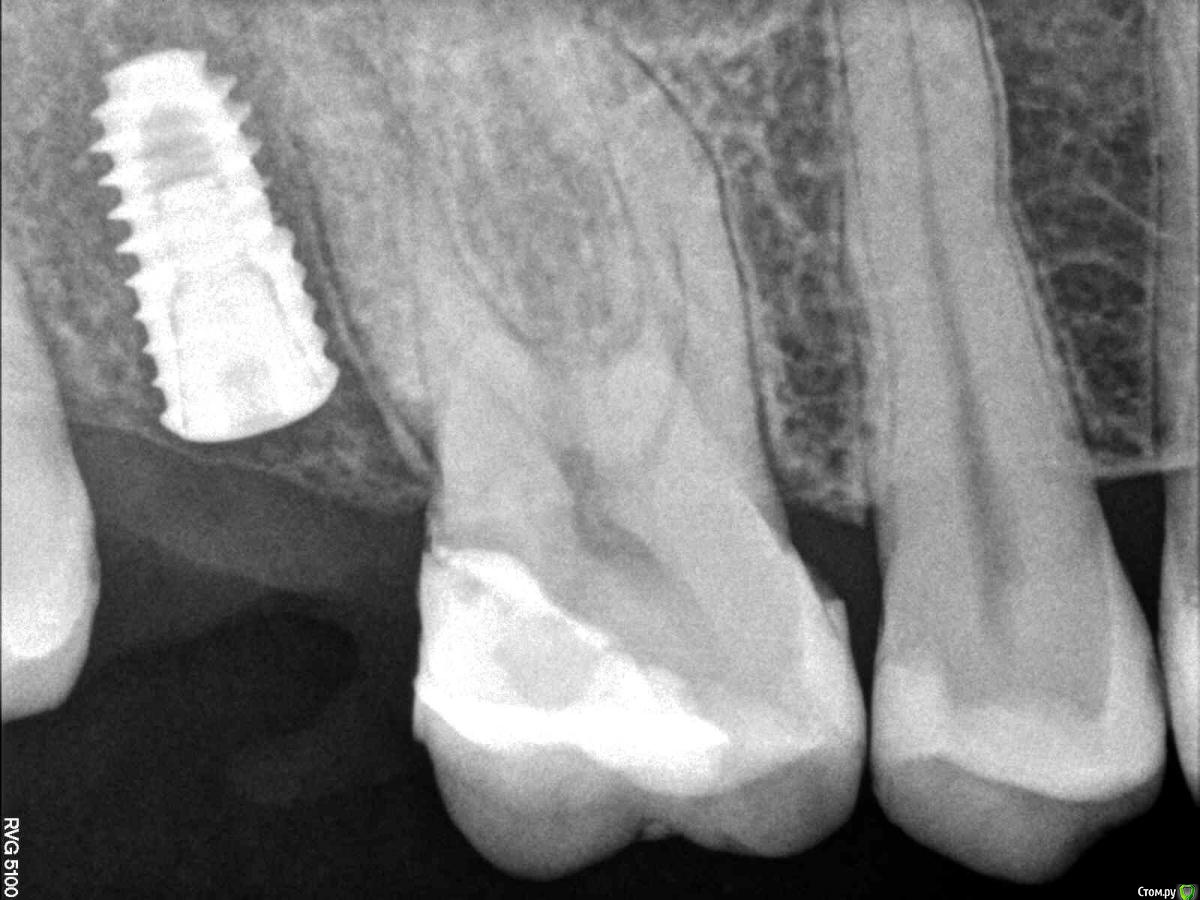

Кариес+ Опубликовано 8 августа, 2016 Поделиться Опубликовано 8 августа, 2016 Установил имплантат осстем , на контрольном рг увидел что очень близко к корню, изменил угол и вышло так как на втором снимке. Будут ли проблемы при протезировании? Ссылка на комментарий

gum Опубликовано 8 августа, 2016 Поделиться Опубликовано 8 августа, 2016 Возможно в первом случае все было хорошо и не надо было переставлять, так как имплантат далеко от небного корня, а щечные могут просто наслаиваться на прицельном снимке. только кт дало бы ответ. по расположению имплантата относительно 6 зуба 1 Ссылка на комментарий